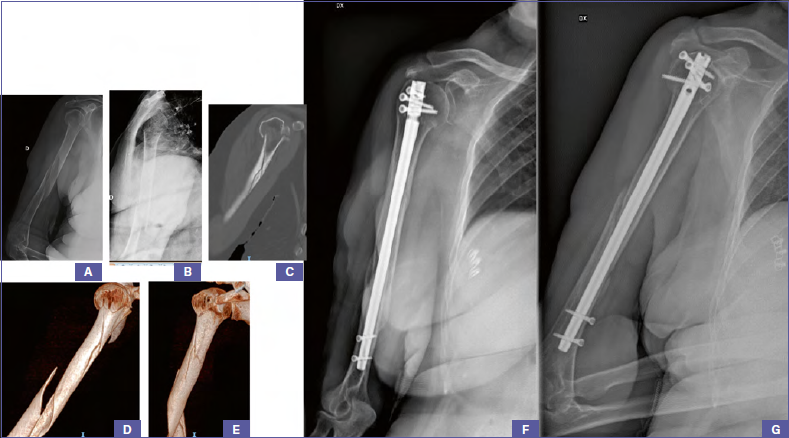

Preservation of the blood supply dependent on surgical technique. Anatomic reconstruction with rigid internal fixation (the carpenter). Fracture fixation of femur midshaft is managed by external fixator, intramedullary nail, or locking plate and screws. Ao principles of fracture management: Copyright by ao foundation, switzerland. Preservation of the blood supply dependent on surgical technique. • fracture personality and patient factors determine fixation construct. The original management objectives were: (2006) principles of fracture fixation. Biomechanics of fractures and fracture fixation. Ao principles of fracture management. It is a type of fracture fixation where the fragments are fixed by a gadget that is buried beneath the soft tissues and is not visible externally. &' fracture fixation providing absolute or relative stability, as required by the personality of the fracture, the patient, and the injury. • in certain articular fractures (e.g. Fracture reduction and fixation to restore anatomical relationships. Intramedullary fixationintramedullary fixation  rotational and axialrotational and axial stability provided bystability provided by interlocking bolts.interlocking bolts. I wanted to understand the principles behind fracture fixation to help me in developing management plans for fractures i had not previously encountered or the seminar sessions are led by two or three consultant orthopaedic surgeons and allow participants to share their experiences and use the ao.